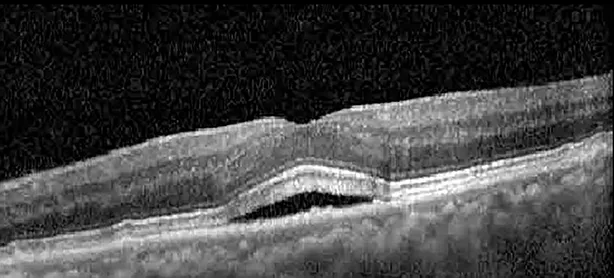

The patient began treatment with oral pemigatinib daily and was followed up for an ophthalmic examination during the second treatment cycle approximately 5 weeks into the treatment process. The patient had at this stage received 28 doses of 13.5 mg per day, which was administered in cycles of 14 on-days and 7 off-days, and had no visual or ophthalmic complaints. The non-corrected VA was OD 20/30 + 1 and OS 20/20. The OCT examinations revealed subfoveal SRF bilaterally. The fundus examination was otherwise unremarkable outside the patient’s prior documented peripheral drusen. Repeat autofluorescence was overall unchanged, though a slight hypofluorescent ring may be visualized in Figure 2. The current pemigatinib protocol recommendation for asymptomatic patients suggests no dose modification; however, with worsening presentation or positive symptoms, it is recommended to withhold pemigatinib. After discussion with the patient’s oncologist, it was decided to continue the medication at this time. Serial monitoring of the patient’s symptoms, vision, and SRF were conducted on specific days during active treatment cycles and days off-cycle to monitor the SRF. Subsequent evaluations demonstrated complete resolution of SRF while off-cycle, and asymptomatic re-accumulation of fluid while on-cycle with varying levels of VA. (Table 1) As we see demonstrated in the table below, in the later stages of the active cycles, such as day 13 of 14 of cycle 2, day 13 of 14 of cycle 3, day 13 of 14 of cycle 4, and day 14 of 14 on cycle 5, the patient’s VA showed no correlative changes based on the presence of SRF. The fluctuations in the patient’s VA certainly occurred, but were likely to be secondary to surface changes, as certain off-cycle days actually presented with lower acuities than days when the SRF was present on OCT examination.

Table 1

| Cycle, day, on/off | VA OD; OS | CMT OD; OS | OCT OD | OCT OS |

| Cycle 2, day 4, off | 20/30−2; 20/20−2 | 282; 280 | ![]() | ![]() |

Highlights the visual acuity, central macular thickness, and the physical OCT of the macula for this patient in both the right and left eyes during various stages of the patient's chemotherapy treatment cycle.